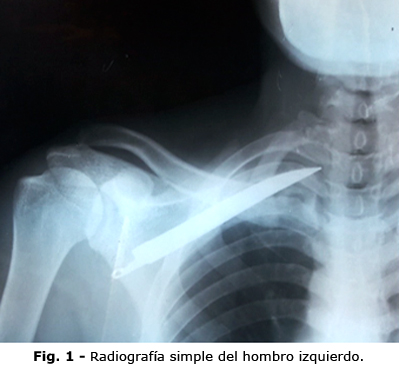

En la radiografía antero-posterior del hombro izquierdo, se observó una imagen radiopaca de densidad metálica, con la forma de una hoja de cuchillo, en proyección subescapular izquierda (Fig. 1).

En la radiografía simple de tórax, vista póstero-anterior y vista lateral izquierda, se comprueba que el cuerpo extraño se encuentra entre la escápula y la pared torácica, lo cual se confirmó con la una tomografía axial computarizada.